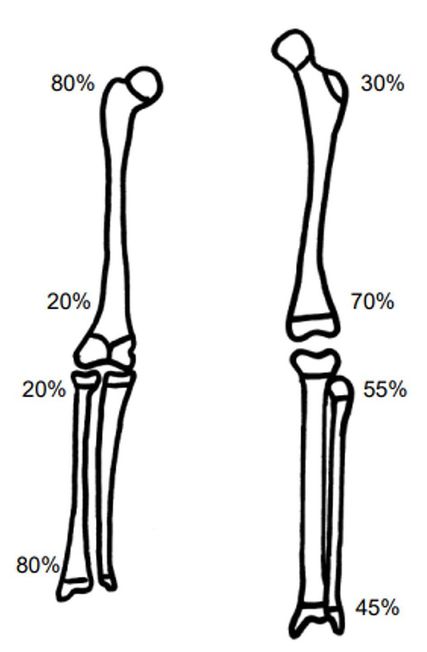

Auch die Frakturlokalisation am Knochen stellt ein wichtiges Kriterium dar. Im Bereich der Metaphyse, also in der Nähe der Wachstumsfuge, besteht eine deutlich höhere Korrekturfähigkeit als an der Diaphyse. Die unterschiedlichen Wachstumspotenziale der frakturnahen Wachstumsfugen gilt es dabei zu berücksichtigen (Abb. 1). Dabei haben Frakturen in der Nähe von hochpotenten Fugen ein größeres Spontankorrekturpotenzial als solche in der Nähe von langsam wachsenden Fugen.

Der wichtigste Faktor in der Beurteilung des Spontankorrekturpotenzials ist jedoch das Alter des Kindes: Je jünger das Kind, desto mehr Spontankorrekturpotenzial ist vorhanden. Zusätzlich zur Lokalisation und zum Alter stellen die funktionelle und statische Belastung sowie die Ebene der Fehlstellung Einflussfaktoren des Remodellings dar.2